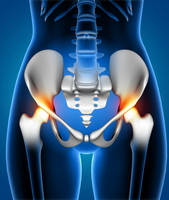

Kalça artroskopisi, kalça eklemi içerisindeki hastalıkların tanı ve tedavisinde kullanılan, minimal invaziv yani kapalı cerrahi bir yöntemdir.